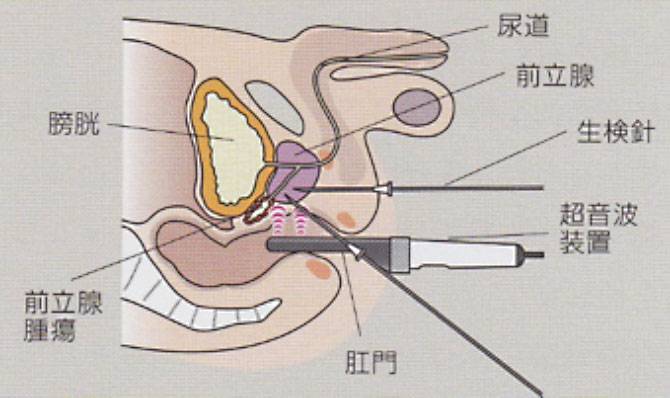

前立腺がん 泌尿器科の病気について 名古屋大学大学院医学系研究科

前立腺がん 腎泌尿器疾患のキーポイント 三重大学大学院 医学系研究

泌尿器疾患 前立腺癌の診断と治療 医師修学資金貸与制度を有する

確定診断までの流れ がんの治療法 詳しく知りたい 前立腺がん

泌尿器科がん 前立腺がん 岡山大学大学院医歯薬学総合研究科泌尿器